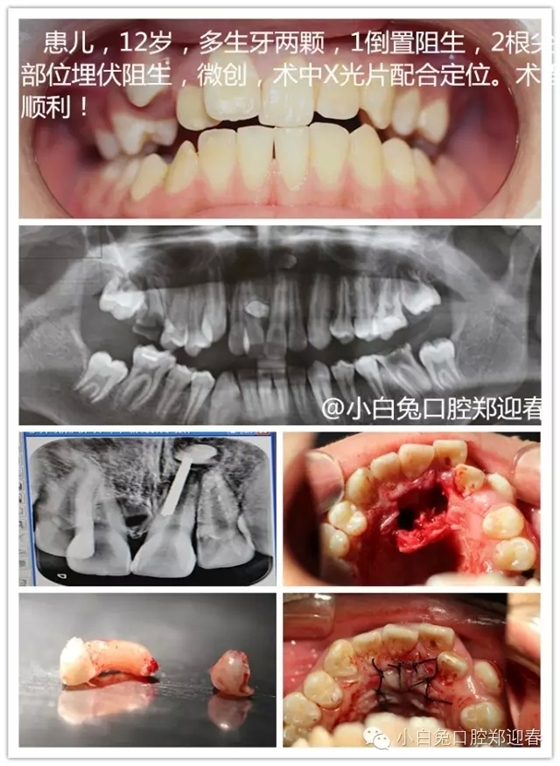

2、難度之最

根尖之下